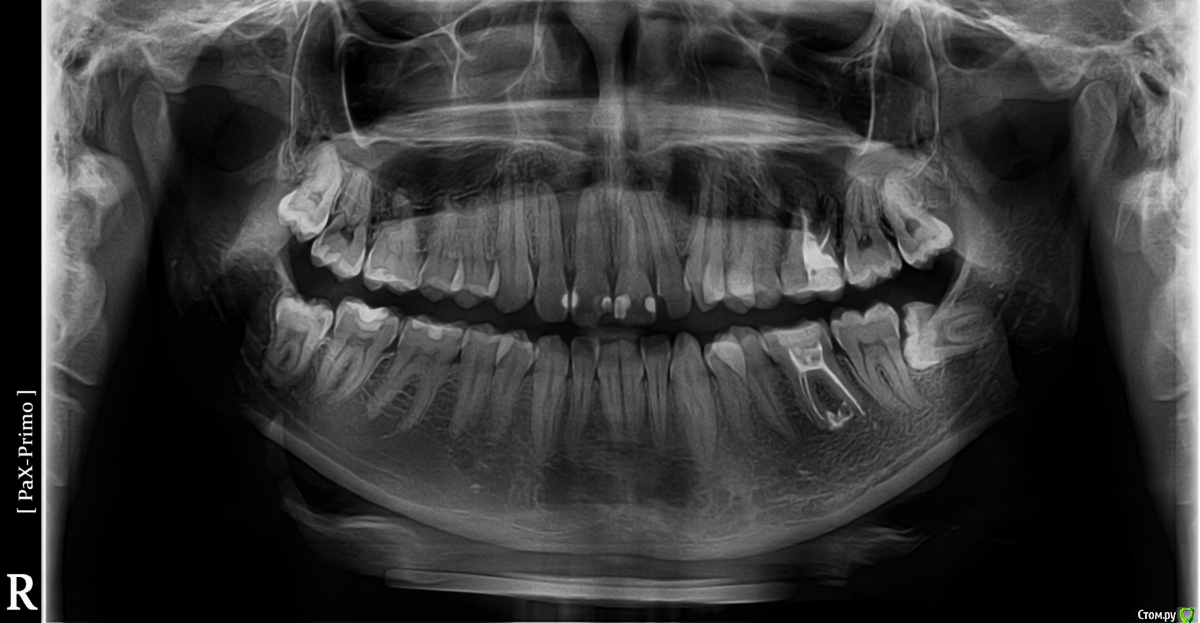

Chelsea Опубликовано 25 апреля, 2018 Поделиться Опубликовано 25 апреля, 2018 (изменено) Добрый день! Намереваюсь поставить брекеты, походил на консультации и разные ортодонты советуют удалять разное количество зубов мудрости. На данный момент уже удалили верхний слева, и точно буду удалять нижний слева. Вопрос - можно ли НЕ удалять восьмерки справа? (их два ортодонты советовали удалять "за компанию", один же требовал удаления всех). С точки зрения ортодонтии - не приведет ли удаление зубов мудрости только с одной стороны к ассиметрии, или к другим последствиям?Снимок прилагается.Спасибо! Изменено 25 апреля, 2018 пользователем Chelsea Ссылка на комментарий